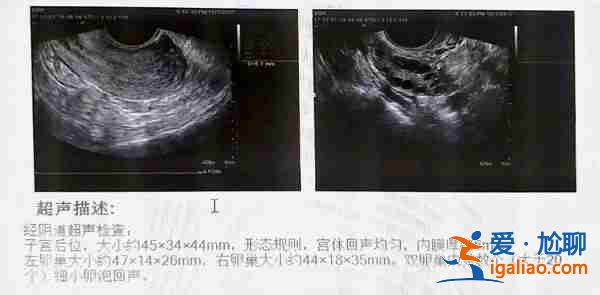

夫妻两做了较为全面的检查,程小姐还算年轻,加上卵巢保养的不错,AMH有4.25,医生制定了长方案,程小姐打了一针降调,过14天返回复查,正式进入促排阶段。